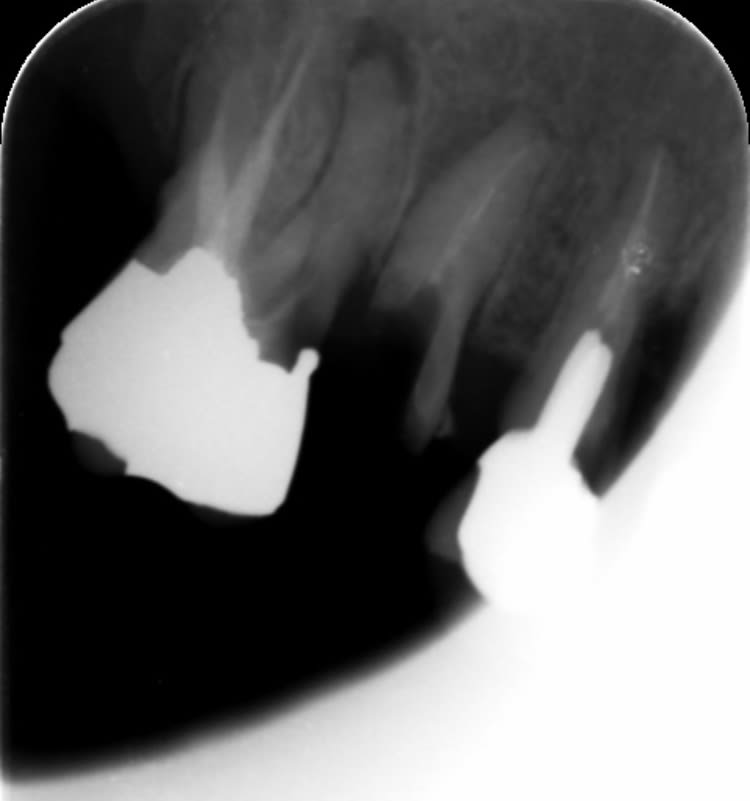

Pas du tout, la lésion n'est pas circulaire et l'entrée punctiforme.

Ce qui est inhabituel, c'est la localisation, c'est vraiment infra, plutôt sphérique, je vous ai marqué la communication avec la poche.

En bouche tu vois rien, ce qui est au dessus est indemne. C'est racine palatine... tenon?